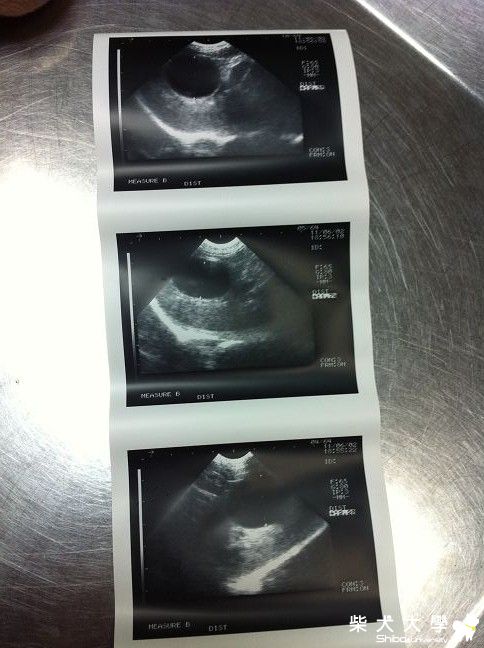

還有照超音波檢查

陰影的部分是膽囊腫大

這是6/2,3 拍攝的